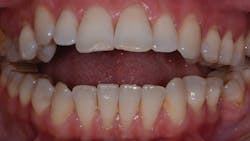

The following clinical case study will demonstrate both of these important principles. A 42-year-old female presents for evaluation of progressive facial and dental occlusion changes (figure 1).